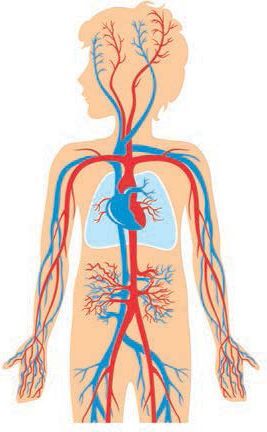

Кровеносная система человека: структура и функции